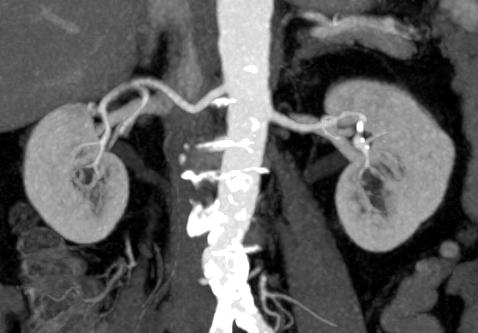

Мультиспиральная КТ сосудов почек (КТ-ангиография) с внутривенным болюсным контрастированием проводится для диагностики патологии почечных артерий. С помощью КТ-ангиографии можно выявить врожденные аномалии развития сосудов почек, диагностировать стенозы (уменьшение просвета) почечных артерий за счет развития атеросклеротических бляшек.

КТ сосудов почек применяется для выявления признаков вторичной артериальной гипертензии, при планировании оперативных вмешательств и для оценки успешности проведенной операции на сосудах. КТ ангиография почечных артерий позволяет оценить их анатомию, выявить добавочные и аберрантные почечные сосуды, определить типично ли они распространяются в ворота почки или заходят в паренхиму через корковый слой.

Чувствительные детекторы улавливают рентгеновские лучи после их прохождения сквозь тело человека. На основании этих данных получаются изображения сосудистой системы почек в мельчайших подробностях. Кроме того, с помощью цифровой обработки данных томограф реконструирует трехмерные модели кровеносных сосудов на уровне исследуемой области. 3D-реконструкции помогают увидеть пространственное соотношение анатомических структур и значительно повышают качество диагностики.

• количество добавочных почечных артерий и варианты их отхождения